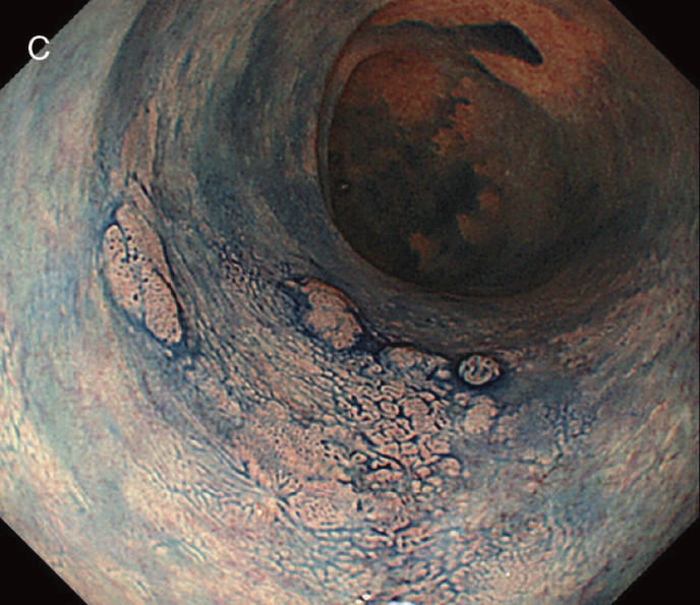

図12 Non-polypoid lesionの内視鏡所見

- 白色光観察

- インジゴカルミン散布像:境界がより明瞭に認識できる。

- 酢酸インジゴカルミン混合液(AIM)散布像:病変全体と周辺粘膜とのコントラストが明瞭となる。

- NBI非拡大観察像:非拡大においても境界の認識は比較的容易となる。

- NIBI拡大観察像:病変中心部では拡張した血管を認める。

- クリスタルバイオレット染色拡大観察像:病変中央では大腸不動の拡張したpitを認める。gの病変辺縁ではpit構造の違いにより周辺粘膜と病変の境界が認識できる。